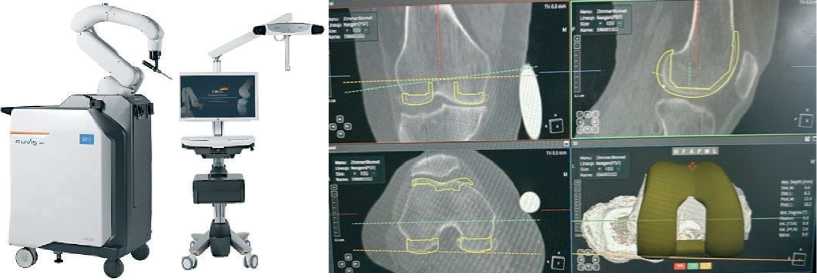

Предоперационное планировани е. Система Cuvis Joint™ – автономная роботизированная платформа для тотального эндопротезирования коленного сустава, основанная на использовании данных КТ. После загрузки изображений в программное обеспечение J-planner™ выполняется автоматическая сегментация и 3D-реконструкция сустава (рис. 1). Хирург определяет центры вращения суставов, осевые соотношения, степень деформации, размеры имплантатов и объёмы костной резекции. На основе данных формируется отчёт о планируемом выравнивании, передаваемый на консоль робота.

Рисунок 1. Слева – робот Cuvis Joint™; справа – ПО J-planner™